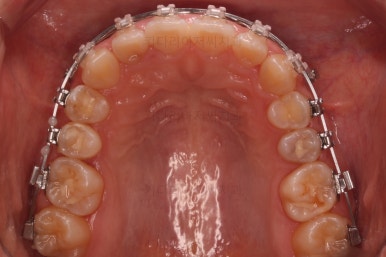

우선 윗니부터 가지런하게 해줍니다.

앞니쪽에는 미니스크류를 식립했는데요.

과개교합 개선, 교합 개선, 거미스마일(잇몸웃음) 개선 등 여러 가지 목적을 동시에 달성할 수 있어요.

윗니가 어느 정도 가지런해지면 아랫니도 장치가 들어갑니다.

과개교합이 어느 정도 개선이 되어서 아래 앞니가 서서히 보이기 시작하네요.

이번 부산옥니교정 환자분이 선택하신 장치는 엠파워인데 윗니는 덜 보이는 세라믹, 아랫니는 메탈입니다.

같은 엠파워 장치이기 때문에 이렇게 섞어 써도 문제가 전혀 없는데요.

흔히 아시는 클리피씨로 하자면 윗니는 클리피씨 + 아랫니는 클리피엠(M)인 셈이죠.

윗니는 세람기으로 해서 심미성을 강조하고 아랫니는 좀 더 부피가 작고 강하여 과개교합 교정에 유리하며 저렴하기도 한 메탈로 했습니다.